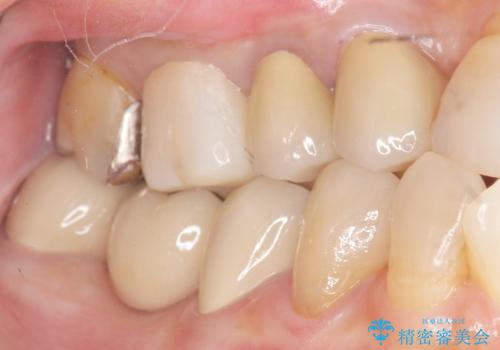

奥歯 抜歯してブリッジに 50代女性

- 奥歯の違和感を主訴に来院された患者様です。

右下の銀歯(右下6)を除去したところ、虫歯が深く保存不可能な状態でした。

ブリッジ、インプラント、入れ歯の3つの選択肢を提案したところ、ブリッジをご希望されました。

抜歯後十分に歯肉の治癒を待ったのち、ブリッジによる補綴治療を行いました。